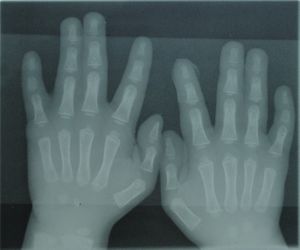

الإصبع[1] finger، هو جزء من اليد، والأصابع موجودة في الإنسان الرئيسيات الأخرى، ويد الإنسان العادية تحتوى على خمس أصابع، وتستخدم الأصابع في كثير من الأنشطة مثل اللمس والإمساك بالأشياء والكتابة. ويُوجد في كلّ إصبعٍ من أصابع الإنسان (باستثناء الإبهام) ثلاث مفاصل، تسمّى عموماً البراجم.

أطراف: ذراع – مرفق – ساعد – رسغ – يد – اصبع (إبهام - سبابة - وسطى - بنصر - خنصر) – رجل – حـِجر Lap – فخذ – ركبة – رَبـْلة الساق Calf muscle – كعب – كاحل – قدم – اصبع قدم (إبهام القدم Hallux)